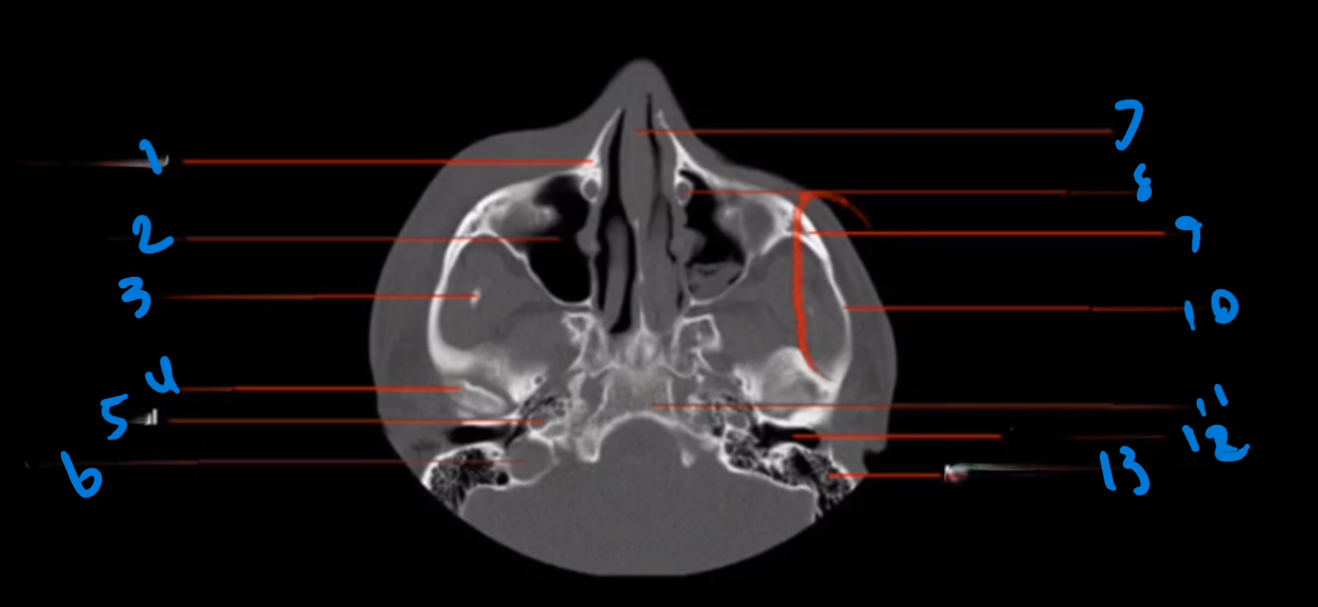

Landmark 1?

Maxillary Bone

Landmark # 2

Maxillary sinus

Landmark #3?

Coronoid process, mandible

Landmark # 4 called?

Mandibular condyle

Landmark # 5?

Carotid Canal

Landmark # 6?

Jugular Foramen

Landmark # 7?

Nasal Septum

Landmark # 8

Nasolacrimal duct

Landmark # 9

Zygoma

Landmark # 10

Zygomatic arch

Landmark # 11?

Clivus

Landmark # 12

External Auditory Meatus

Landmark # 13

Mastoid Air Cells, Temporal Bone